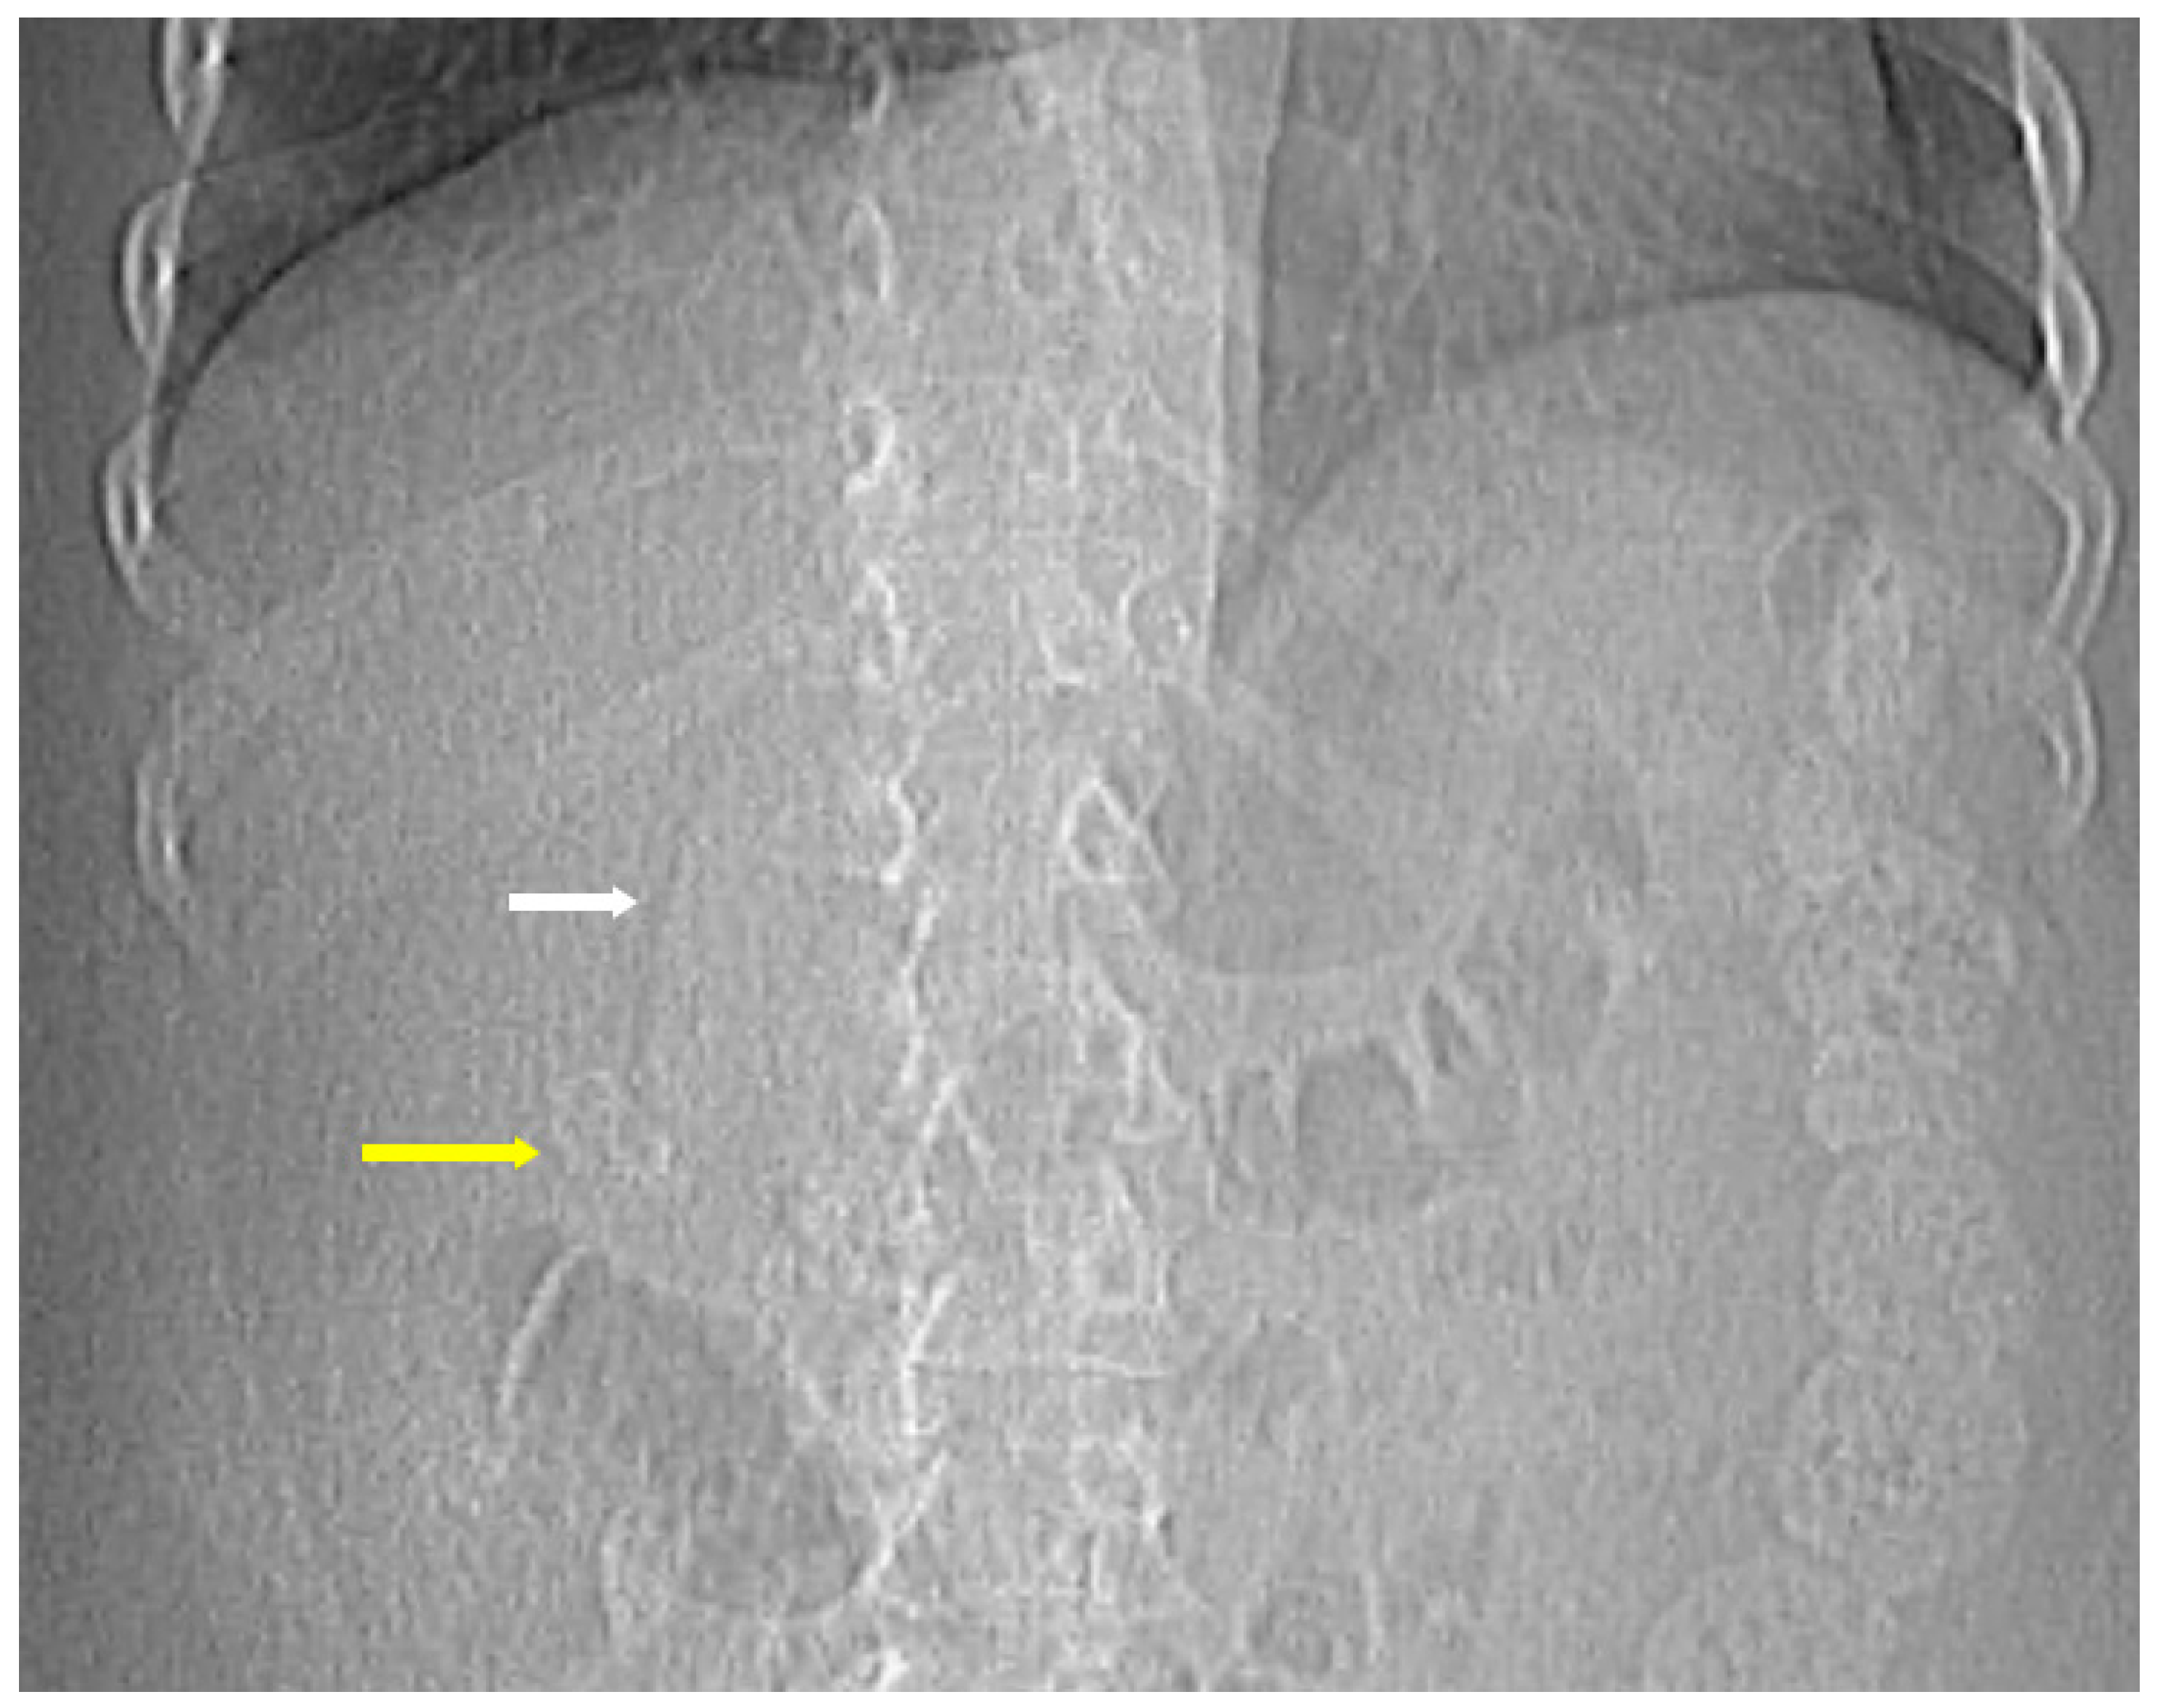

The classic findings on plain radiographs include emphysematous mural gas within the gallbladder wall, intraluminal gas, and pericholecystic gas, which may appear as curvilinear lucencies outlining the gallbladder or as mottled, air-fluid levels in the RUQ [13]. Free intraperitoneal air may also be seen if perforation has occurred. Patient positioning can aid in EC diagnosis because gas redistributes to the nondependent portion and may rise or layer, demonstrating mobility on decubitus or upright imaging.

A supine abdominal radiograph may show crescent-shaped or linear lucencies corresponding to gas within the gallbladder wall. In some instances, the gallbladder outline becomes visible due to the presence of gas surrounding it. Erect radiographs may also reveal air-fluid levels in the RUQ if intraluminal gas has accumulated [13,14]. The presence of gas in these locations seen on imaging may have been introduced during procedures or surgeries such as endoscopic retrograde cholangiography, post sphincterotomy or choledocho-enteric anastomosis, so knowledge of a patient’s clinical and surgical history is essential.

The hallmark CT findings of EC include the presence of gas within the gallbladder wall, lumen, or pericholecystic tissues. Gas may appear as curvilinear, punctate, or mottled foci along the gallbladder wall, as seen in Figure 3, Figure 4 and Figure 5. Intraluminal gas can create air-fluid levels or completely fill the gallbladder, while gas in adjacent tissues may signify transmural necrosis or perforation [7]. CT can also identify complications such as pericholecystic abscess, emphysematous spread to adjacent organs (e.g., liver or duodenum), or intraperitoneal free air in the case of perforation and rupture [18].

Figure 3. The initial scout image of a computed tomography abdomen and pelvis for a 49-year-old female diabetic patient. Curvilinear lucencies (white arrow) outlining the gallbladder due to emphysematous mural gas within the gallbladder wall and cholelithiasis (yellow arrow) were demonstrated.